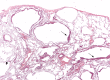

Surgical lung biopsy showing several thin-walled rounded cysts of varying dimensions. The LAM cells form small plaques in the wall of the cysts (arrows) (haematoxylin–eosin, 20×). Figure courtesy of A. Cavazza.